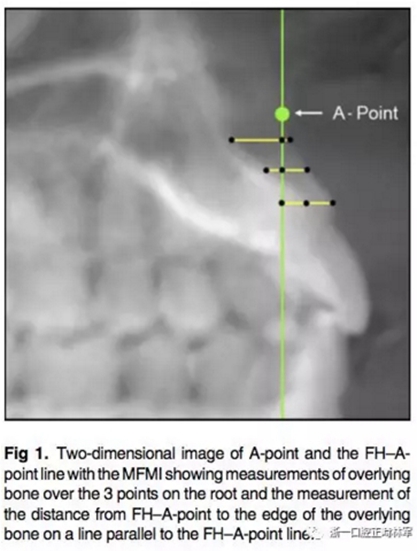

所有圖像導(dǎo)入Dolphin軟件中進(jìn)行處理,2D側(cè)位圖像為使用Dolphin軟件使用相同的標(biāo)準(zhǔn)切割CBCT獲得。使用眶耳平面(FH)作為水平參考平面,使用垂直于眶耳平面(FH)同時(shí)通過A點(diǎn)的直線作為垂直參考平面。在上切牙最前點(diǎn)進(jìn)行定點(diǎn),牙根分界為自釉牙骨質(zhì)界至根尖,在牙根根尖、牙長(zhǎng)1/2處、釉牙骨質(zhì)界下3mm處進(jìn)行定點(diǎn)。使用FH的平行線測(cè)量頰側(cè)牙槽骨至牙根上3點(diǎn)的距離,同時(shí)測(cè)量A點(diǎn)與以上三條線段的距離,如圖所示。測(cè)量切牙的轉(zhuǎn)矩,使用通過切點(diǎn)、根尖的直線與FH平面的所成角。

根據(jù)每顆切牙相對(duì)上頜骨的位置在同一平行切面上各自確定A點(diǎn),定好切牙最前點(diǎn)(MFMI),牙根長(zhǎng)度依然為釉牙骨質(zhì)界至根尖點(diǎn)。使用與2D側(cè)位片上相同的方法進(jìn)行牙根至骨皮質(zhì)的測(cè)量。轉(zhuǎn)矩的測(cè)量也同2D側(cè)位片。